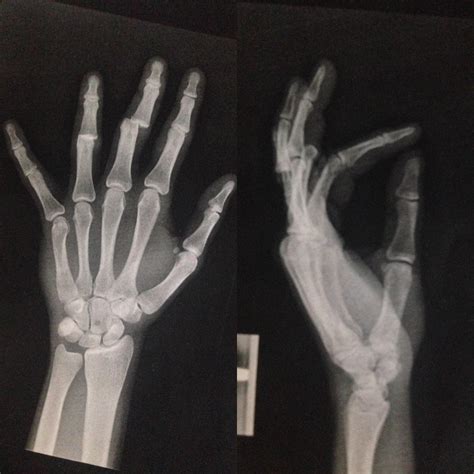

Diagnosing a Dislocated Small Finger

If you suspect a dislocated small finger, it is crucial to seek medical attention promptly. A healthcare professional will perform a physical examination and may order imaging tests to confirm the diagnosis. Common diagnostic methods include:

• X-rays: To visualize the bones and determine the extent of the dislocation.

• Deformity: Visible deformity or misalignment of the finger.